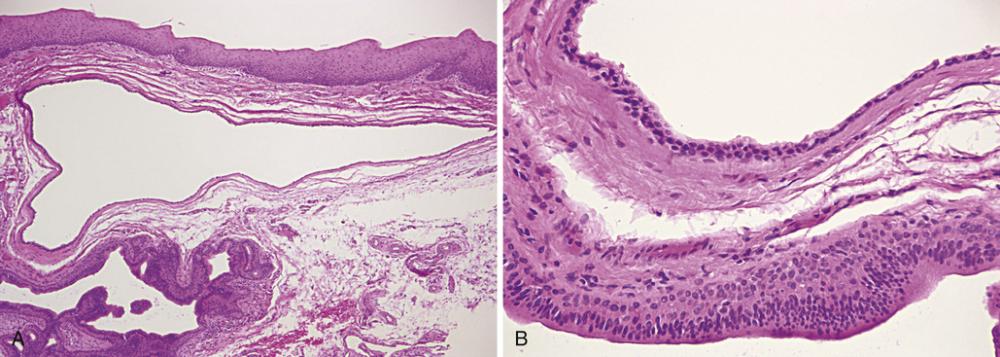

- Low-power photomicrograph showing a cyst below the mucosal surface.

- High-power view of cystic cavity lined by thin cuboidal epithelium. Adjacent to the cyst is an excretory salivary gland duct lined by columnar epithelium.

salivary duct cyst